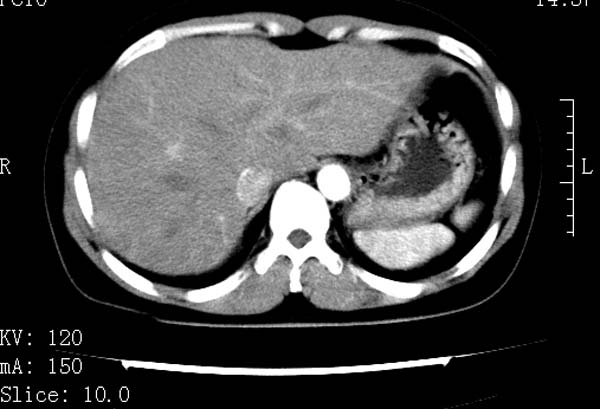

标题: CT22086:女44岁 肝右叶占位增强示巨大血管瘤,门脉期发现小 [打印本页]

标题: CT22086:女44岁 肝右叶占位增强示巨大血管瘤,门脉期发现小

支持肝右叶血管瘤诊断。 小病灶亦考虑血管瘤改变。温习一下:

肝海绵状血管瘤ct平扫常呈均匀低密度,与邻近血管密度相仿。在脂肪肝背景下可呈相对高密度。在增强扫描时,一般早期(动脉期)呈周边结节状或弧形强化,其密度与同层面的血管密度相仿,随着时间延迟向中央渐进性充填,注药后5~7分钟,逐渐扩大至全瘤强化,强化密度逐渐降至稍高于或等于正常肝脏。大的血管瘤往往中央有星形、大的低密度区,可以为纤维化或囊性变所致,纤维化成分可在延迟2 o分钟时完全充填,呈等密度,但囊变区则不会强化。不典型ct表现常见于≤3 cm的小血管瘤。小的血管瘤可以在动脉期即呈全部致密的均匀强化,不呈典型的周边结节状强化表现,但其密度往往较高,与主动脉相仿,在延迟期呈高或等密度。其他不典型的ct表现有:增强扫描强化不明显,呈点状较轻程度的强化,充填慢,可能与供血动脉较细和较大的血管间隙有关以及中央先强化等。

延迟扫描三个病灶都呈等密度改变。肝多发血管瘤,较典型。